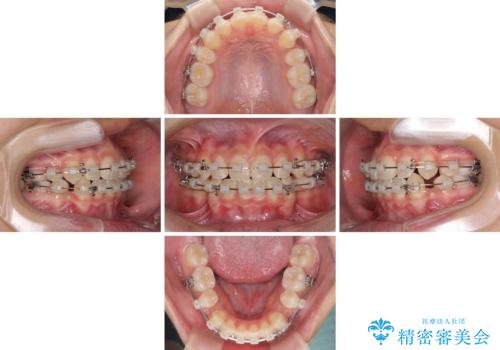

- クリアブラケット

- 2年4ヶ月

口元に力の入る歯列であったため、上顎左右第一小臼歯4本を抜歯するワイヤー矯正を行うこととしました。

当初は八重歯やデコボコが一番気になっていましたが、抜歯矯正により口元の突出感が改善されるにつれ、口の閉じやすさを実感するようになってきました。

部活動で調整来院に来られないことがしばしばあり、期間は予定よりもかかりましたが、きれいに仕上げることができました。